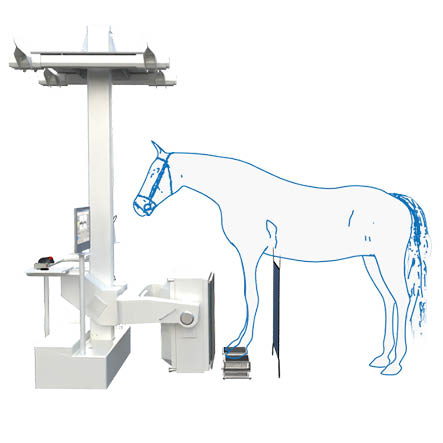

Scintigraphy on a Standing Horse

An ingenious combination of mechanics, electronics, and software makes scintigraphy on a standing horse easily achievable. Experience gained from human medicine, including detector specifications, measurement methods, and processing, as well as feedback from our many customers, has enabled us to achieve the goal of easy and fast diagnosis.

It is compact, robust, and mechanically superior to pendulum suspension systems. The detector support column is mounted approximately one centimeter above the floor, allowing quick and easy movements along any axis of the gantry support. Thus, the gantry operates at a low noise level.